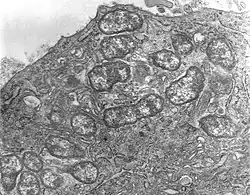

Orientia tsutsugamushi is a Gram-negative bacterium and is a permanent (obligate) parasite in mites. Within a single host cell, O. tsutsugamushi rapidly divides into many individuals. A unicellular organism, it is oval shaped and measures 0.5 to 0.8 μm wide and 1.2 to 3.0 μm long. Due to similarity, it was previously classified in the genus Rickettsia among other bacteria, but later assigned a separate genus, Orientia,[20] which it shares (as of 2010) only with Candidatus Orientia chuto.[21] It is broader but shorter than other rickettsial bacteria, which are rod shaped and on average measure 0.25 to 0.3 μm wide and 0.8 to 1 μm long.[22] During reproduction, it divides (by binary fission) into two daughter cells by the process of budding. While undergoing budding, it accumulates on the host cell surface, unlike other bacteria. One complete budding cycle takes 9 to 18 hours.[23]

Orientia tsutsugamushi has a special adaptation for surviving in the host cell by evading the host immune reaction. Once it interacts with the host cells, it causes the host cell membrane to form a transportation bubble called a clathrin-coated vesicle by which it gets transported into the cytoplasm. Inside the cytoplasm, it makes an exit from the vesicle (now known as an endosome) before the endosome is destroyed (in the process of cell-eating called autophagy) by the lysosomes.[42] It then moves towards the nucleus, specifically at the perinuclear region, where it starts to grow and multiply. Unlike other closely related bacteria which use actin-mediated processes for movement in the cytoplasm (called intracellular trafficking or transport), O. tsutsugamushi is unusual in using microtubule-mediated processes similar to those employed by viruses such as adenoviruses and herpes simplex viruses. Further, the escape (exocytosis) from an infected host cell is also unusual. It forms another vesicle using the host cell membrane, gives rise to a small bud, and releases itself from the host cell surface while still enclosed in the vesicle. The membrane-bound bacterium is formed by interaction between cholesterol-rich lipid rafts as well as HtrA, a 47-kDa protein on the bacterial surface.[43] However, the process of budding and importance of the membrane-bound bacterium are not yet understood.[44][45]